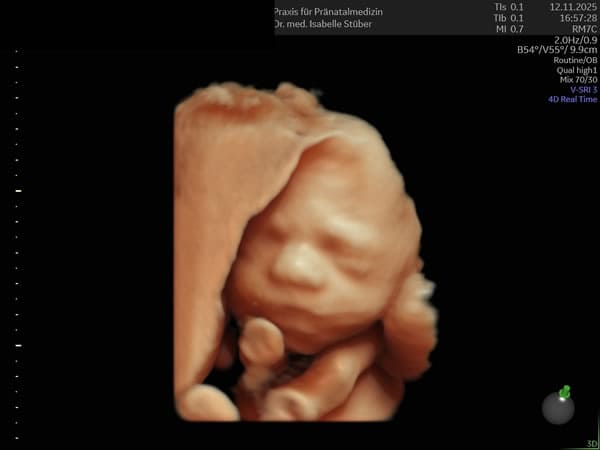

Im zweiten Trimenon bieten wir ab der 21. SSW einen ausführlichen Organultraschall mit modernsten Ultraschallgeräten an.

Ziel ist es, sämtliche Organe des Kindes genau zu untersuchen, um Fehlbildungen auszuschließen oder frühzeitig zu erkennen. Bestandteil ist die Untersuchung des kindlichen Herzens und die Dopplersonographie.